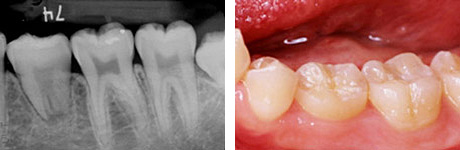

移植後8ヶ月。